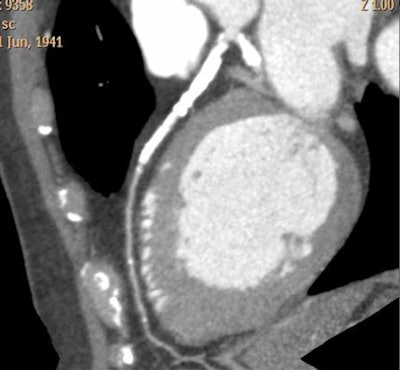

|  |

| CTA interpretation is complicated by heavy coronary artery calcification; flow analysis could potentially aid diagnosis in such cases. All images courtesy of Dr. Henning Bovenschulte. |